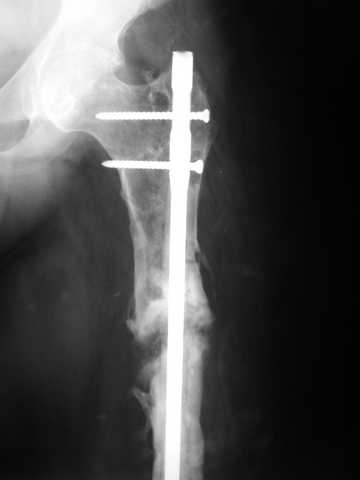

Мы демонтировали спице-стержневой аппарат, рассверлили костно-мозговой канал (до 14 мм), установили в канал спейсер с антибиотиком и произвели его блокирование четырьмя винтами ( рис. 1, 2, 3, 4).

В качестве армирующего элемента для спейсера мы использовали титановый неканюлированный штифт типа UFN (диаметр 9 мм, длина 400 мм). Проксимальную широкую часть штифта костным цементом не покрывали (рис. 5).

Дистальные блокирующие отверстия в цементе рассверлили после его застывания под ЭОП'ом. В проксимальном отломке использовали винт-полер (так как штифт проходил очень близко к переднему кортикальному слою).